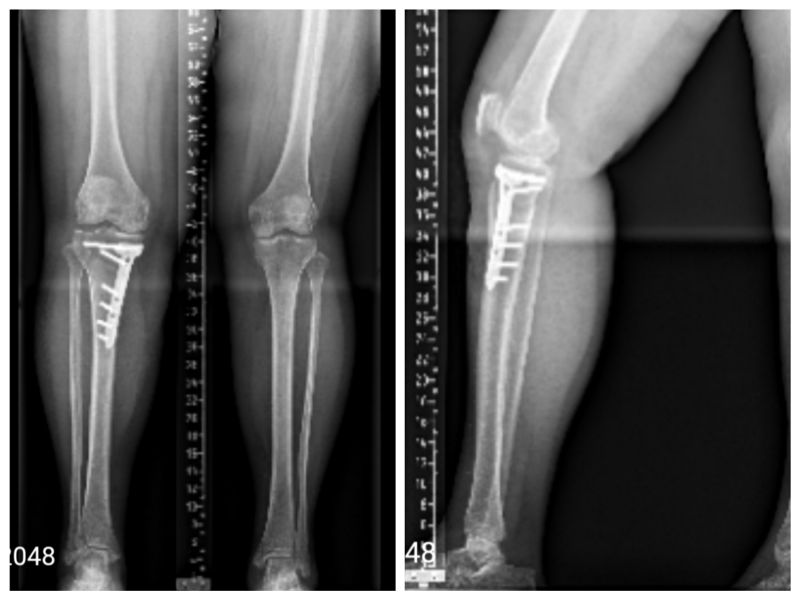

HTO截骨术后

经过细致的术前准备,在麻醉科、手术室的大力配合下,手术团队用时一个小时就顺利完成了该手术。术中,医生对患者关节内损伤的半月板进行了修整成形,并且完成了胫骨内侧高位截骨及撑开固定,从而精准纠正患者下肢力线,将患者负重区域由膝关节内侧调整到膝关节外侧,显著改善了膝关节内侧间室疼痛的症状,患者术后第二天即可下地活动,对手术效果十分满意。